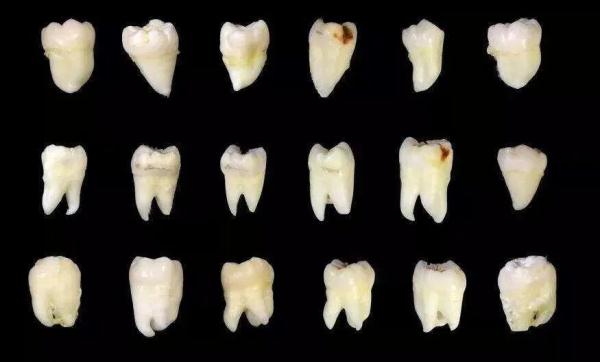

从下图可见,这些是被拔去的相对完整智齿,而更多的智齿其实已经在拔牙过程中四分五裂。即便如此,这些幸存下来的智齿,或多或少也已经出现了各种龋损和破坏。

虽说大多数被拔的智齿

都或多或少会引起、

或曾经引起疼痛